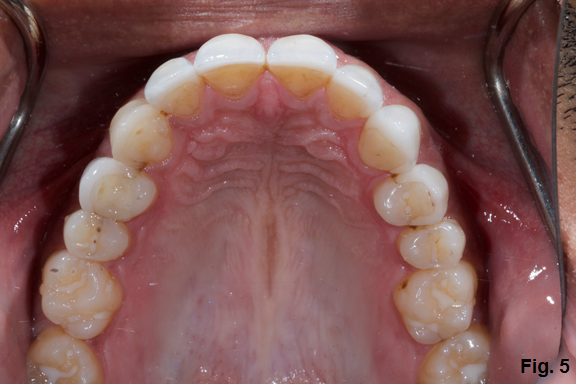

Additionally, if you look at his posterior teeth, you will notice that he doesn’t have much wear behind the canines. (Fig. 5)

Next we look at function; we already know that there is wear, and that he knows that he clenches and possibly grinds. We also know that there is very little wear on the back teeth, which means he probably is not grinding at night – but that doesn’t rule out clenching. There is fremitus of the anteriors when the patient taps his teeth together, meaning there is slight mobility. We know that we need more overjet to create better function.